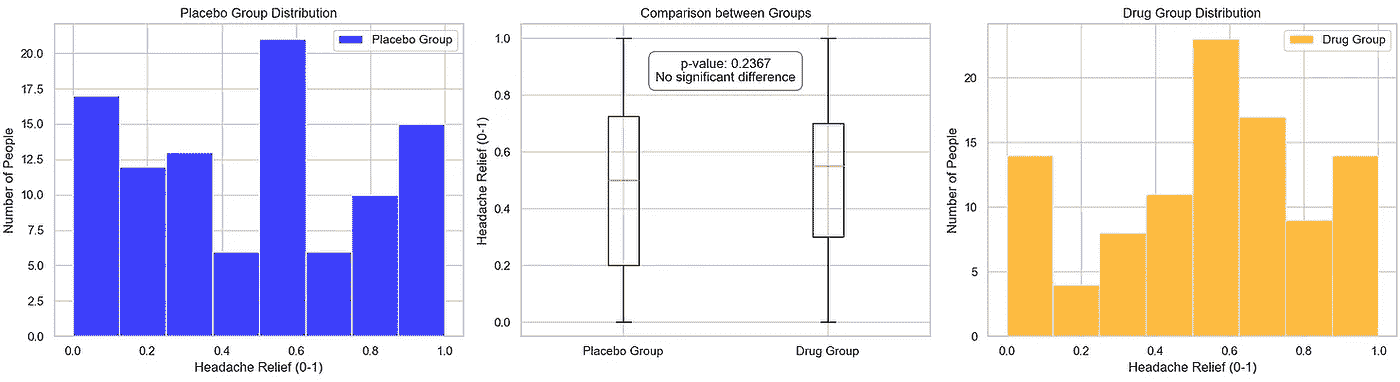

下面,我们查看两种情景:一种是 p 值较大,表明在零假设下观察结果与预期结果之间没有显著差异;另一种是 p 值表明两组之间存在显著差异。

情景 1:显著的 p 值,观察结果与预期结果之间没有显著差异

由于我们的目标不是进行实际的临床试验,我们通过为安慰剂组和药物组设计使用均匀分布的情景来模拟试验,然后将其引入我们的 pvalue_significance_estimator 函数中。

placebo_group = [round(random.uniform(0, 1), 1) for _ in range(100)] # Placebo group data

drug_group = [round(random.uniform(0, 1), 1) for _ in range(100)] # Drug group data

pvalue_significance_estimator(placebo_group, drug_group)

图片由作者提供

当我们可视化结果时,我们观察到在中央子图中,两组的均值相对接近,导致了一个较大的 p 值(约 0.24)。检查数据后,似乎两组具有相似的头痛缓解属性。